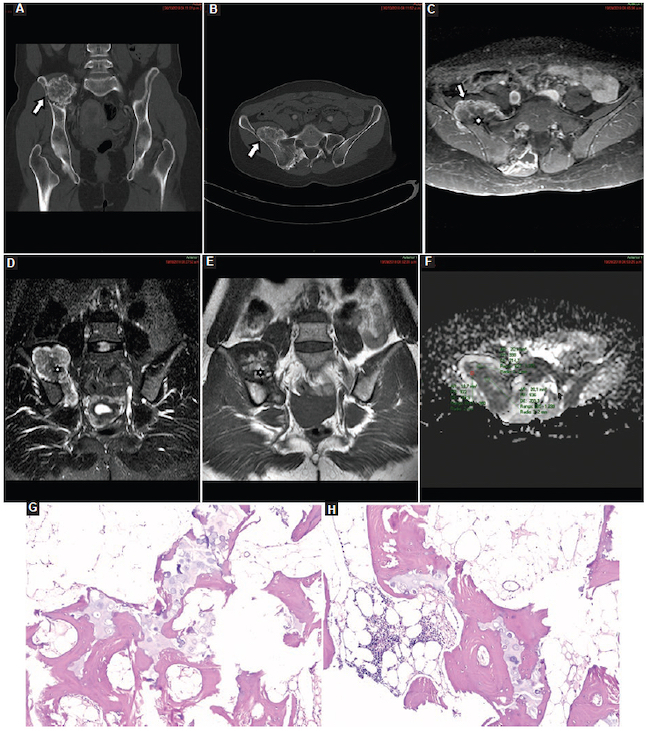

Para las biopsias se utilizaron agujas dedicadas para cada tejido. Cuando las lesiones fueron de partes blandas se procedió con guía ecográfica con un equipo Mindray Resona 7 (Mindray Headquarter, Shenzhen, República Popular de China), con transductor de alta frecuencia, y se utilizaron agujas de corte tipo Tru-Cut de 14 o 16 G con una longitud de 10 cm (dependiendo del tamaño de la lesión), montadas en una pistola de disparo automático a doble armamento (Fig. 2). Cuando las lesiones fueron óseas se procedió con guía tomográfica con un equipo Siemens Somatom Sensation de 64 Canales (Alemania, Erlangen) y se utilizaron agujas de punción ósea para médula ósea de 11 × 4 G (Fig. 3).

Para ambos procedimientos se utilizaron campo estéril, guantes estériles, jeringa de 5 ml tipo Terumo y aguja de 21 G para la instilación de anestésico local (lidocaína al 2%, 5 ml). Una vez adquirida la muestra, se colocó en un frasco estéril con formol al 10%. Cada frasco fue correctamente rotulado con la fecha de la biopsia y la correspondiente hoja de identificación (datos del paciente, sitio de punción, cantidad de muestras y diagnóstico presuntivo por imágenes).

Condrosarcomas: fueron seis casos, con un valor medio de CDA de 0,90 ± 0,06 × 10−3 mm2/s (0,801,00) (Fig. 16), de los cuales fueron tres en el húmero, dos en el fémur y uno en la pelvis.